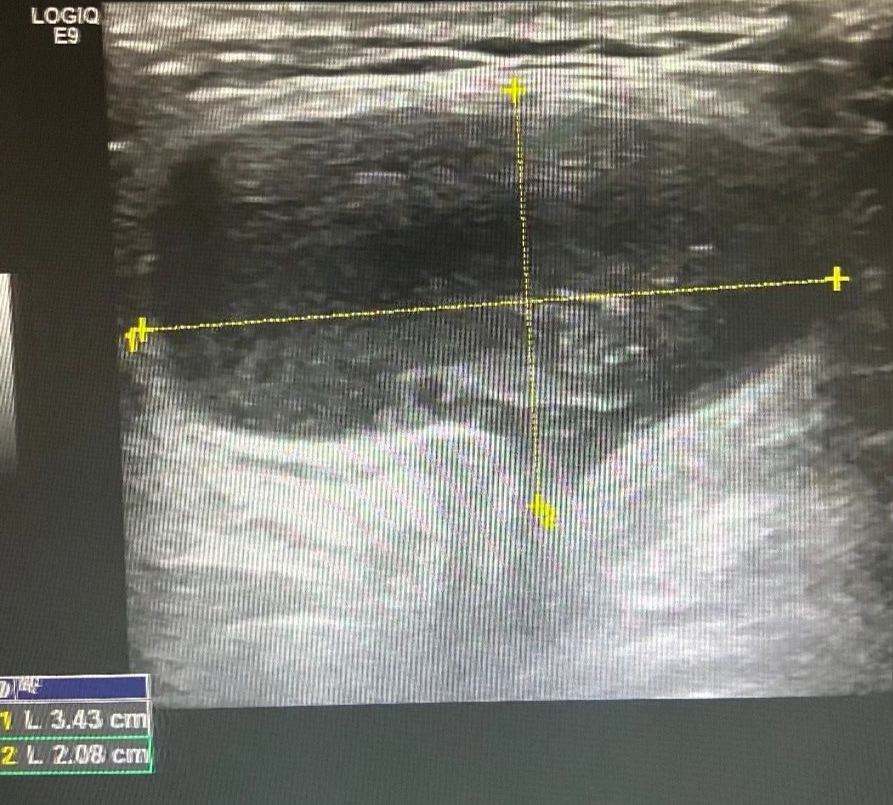

图 5 左侧腹股沟区包块

站立位探查:左侧腹股沟区见范围约 3.3cm×2.0cm×0.9cm 无回声区,透声欠佳,内可见分隔,平卧位变化不明显。右侧腹股沟区未见明显异常回声。

超声提示

左侧腹股沟无回声区,子宫圆韧带囊肿?

术后证实为左侧子宫圆韧带囊肿。